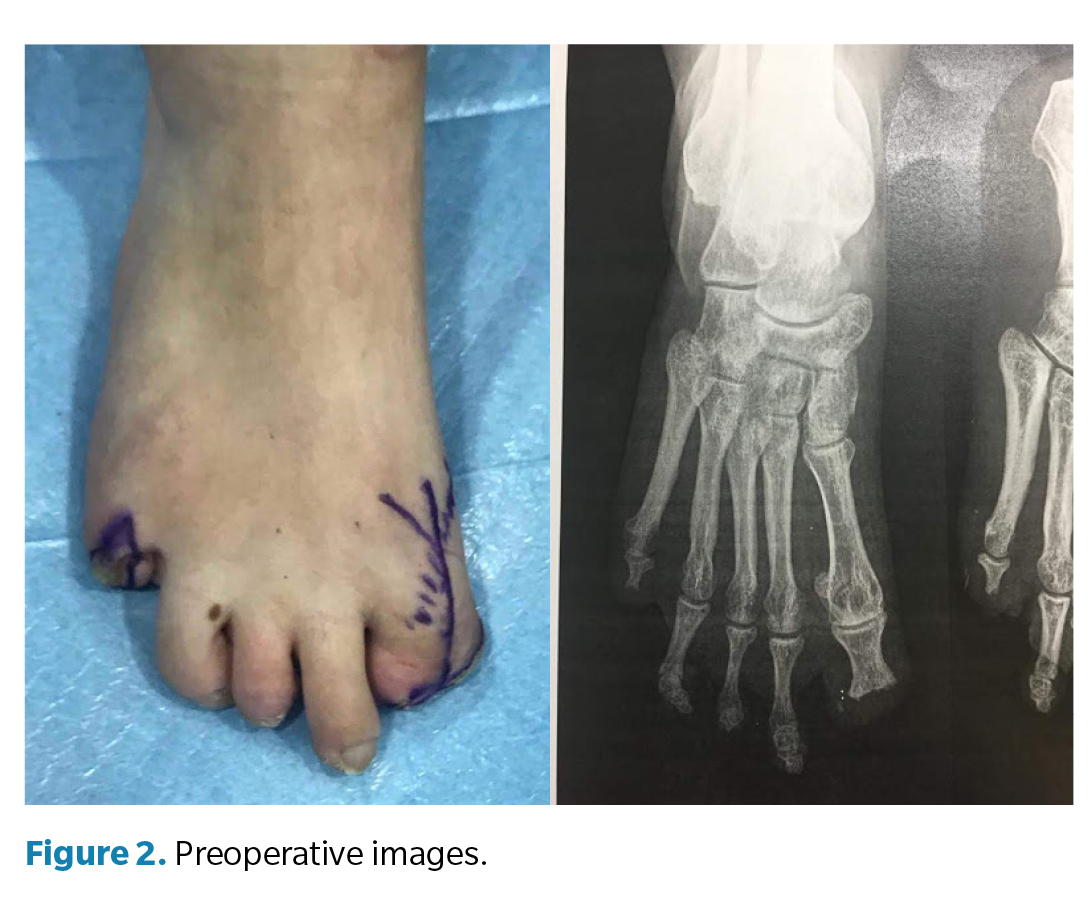

Clinical examination (Figure 2) of the right foot revealed a rigid first metatarsophalangeal joint, with the hallux in fixed plantar flexion and absence of the distal phalanx, producing a painful stump and altered propulsion during gait. The deformity was interpreted as a result of postamputation shortening and cicatricial fibrosis of the residual flexor, with no distal traction. Direct pressure elicited pain over the residual tip of the first toe, which was deformed but retained limited joint mobility. The right fifth toe had a painful hypertrophic scar with a residual corn secondary to total amputation. The left foot showed normotrophic scars at the partial amputation sites of the second and third toes, with no pain or plantar overload, thus requiring no surgery.

Surgery (Figure 3) was performed in March 2022 under regional anesthesia using a posterior popliteal block and conscdious sedation supervised by an anesthesiologist. Antibiotic prophylaxis with 2 g of IV cefazolin was administered 30 minutes before incision, and a pneumatic ankle tourniquet was applied (250 mm Hg), with controlled pressure and ischemia time limited to 45 minutes. A longitudinal dorsal approach to the first metatarsophalangeal joint was performed, preserving neurovascular structures. Irregular bony remnants of the proximal phalanx were identified and completely resected, followed by contouring of bone margins to achieve smooth, viable surfaces. Articular surfaces of the first metatarsophalangeal joint were then prepared by burring and curettage until an adequate bleeding base for arthrodesis was obtained. Fusion position was determined intraoperatively under load testing, fixing the hallux at approximately 10° dorsiflexion relative to weightbearing surface to optimize propulsion and prevent plantar overload on the residual stump. Final fixation was achieved using one cannulated compression screw, ensuring intraoperative stability and correct alignment under fluoroscopy (Figure 4). The procedure concluded uneventfully, with meticulous hemostasis and layered closure.